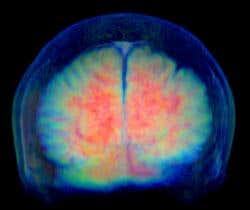

THE quest to understand the most complex object in the known universe has been a long and fruitful one. These days we know a good deal about how the human brain works – how our senses translate into electrical signals, how different parts of the brain process these signals, how memories form and how muscles are controlled. We know which brain regions are active when we listen to speech, look at paintings or barter over money. We are even starting to understand the deeper neural processes behind learning and decision-making.

Perhaps it is. The brain is much messier than a physical system. It is the product of half a billion years of evolution. It performs myriad functions – reasoning, memory, perception, learning, attention and emotion to name just a few – and uses a staggering number of different types of cells, connections and receptors. So it does not lend itself to being easily described by simple mathematical laws.